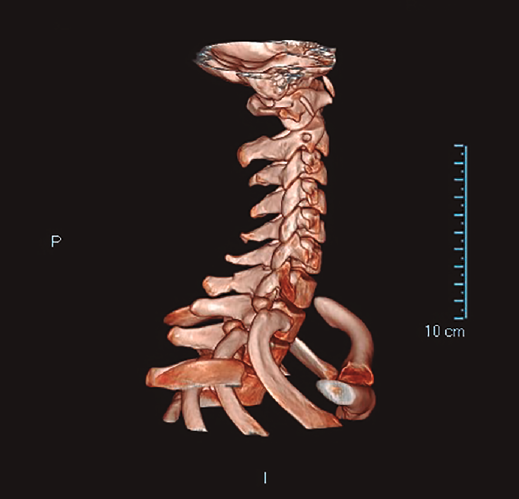

Se solicitó estudio radiográfico(3) y tomografía computarizada (TC)(4) de la columna cervical donde se apreció una fractura con ligera desviación de fragmentos de la apófisis espinosa de C7 (Figuras 1 y 2).

Figura 2. Fractura con ligera desviación de fragmentos de la apófisis espinosa de C7.